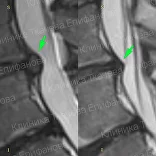

* Резорбция — процесс уменьшения грыжи диска за счет естественных физиологических способностей организма. Это основа эффективного лечения грыжи и альтернатива операции.

Метод модулируемой резорбции позволяет ускорить этот процесс, взять боль под контроль и улучшить качество жизни.